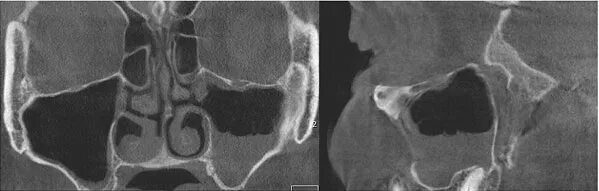

Синусит на кт